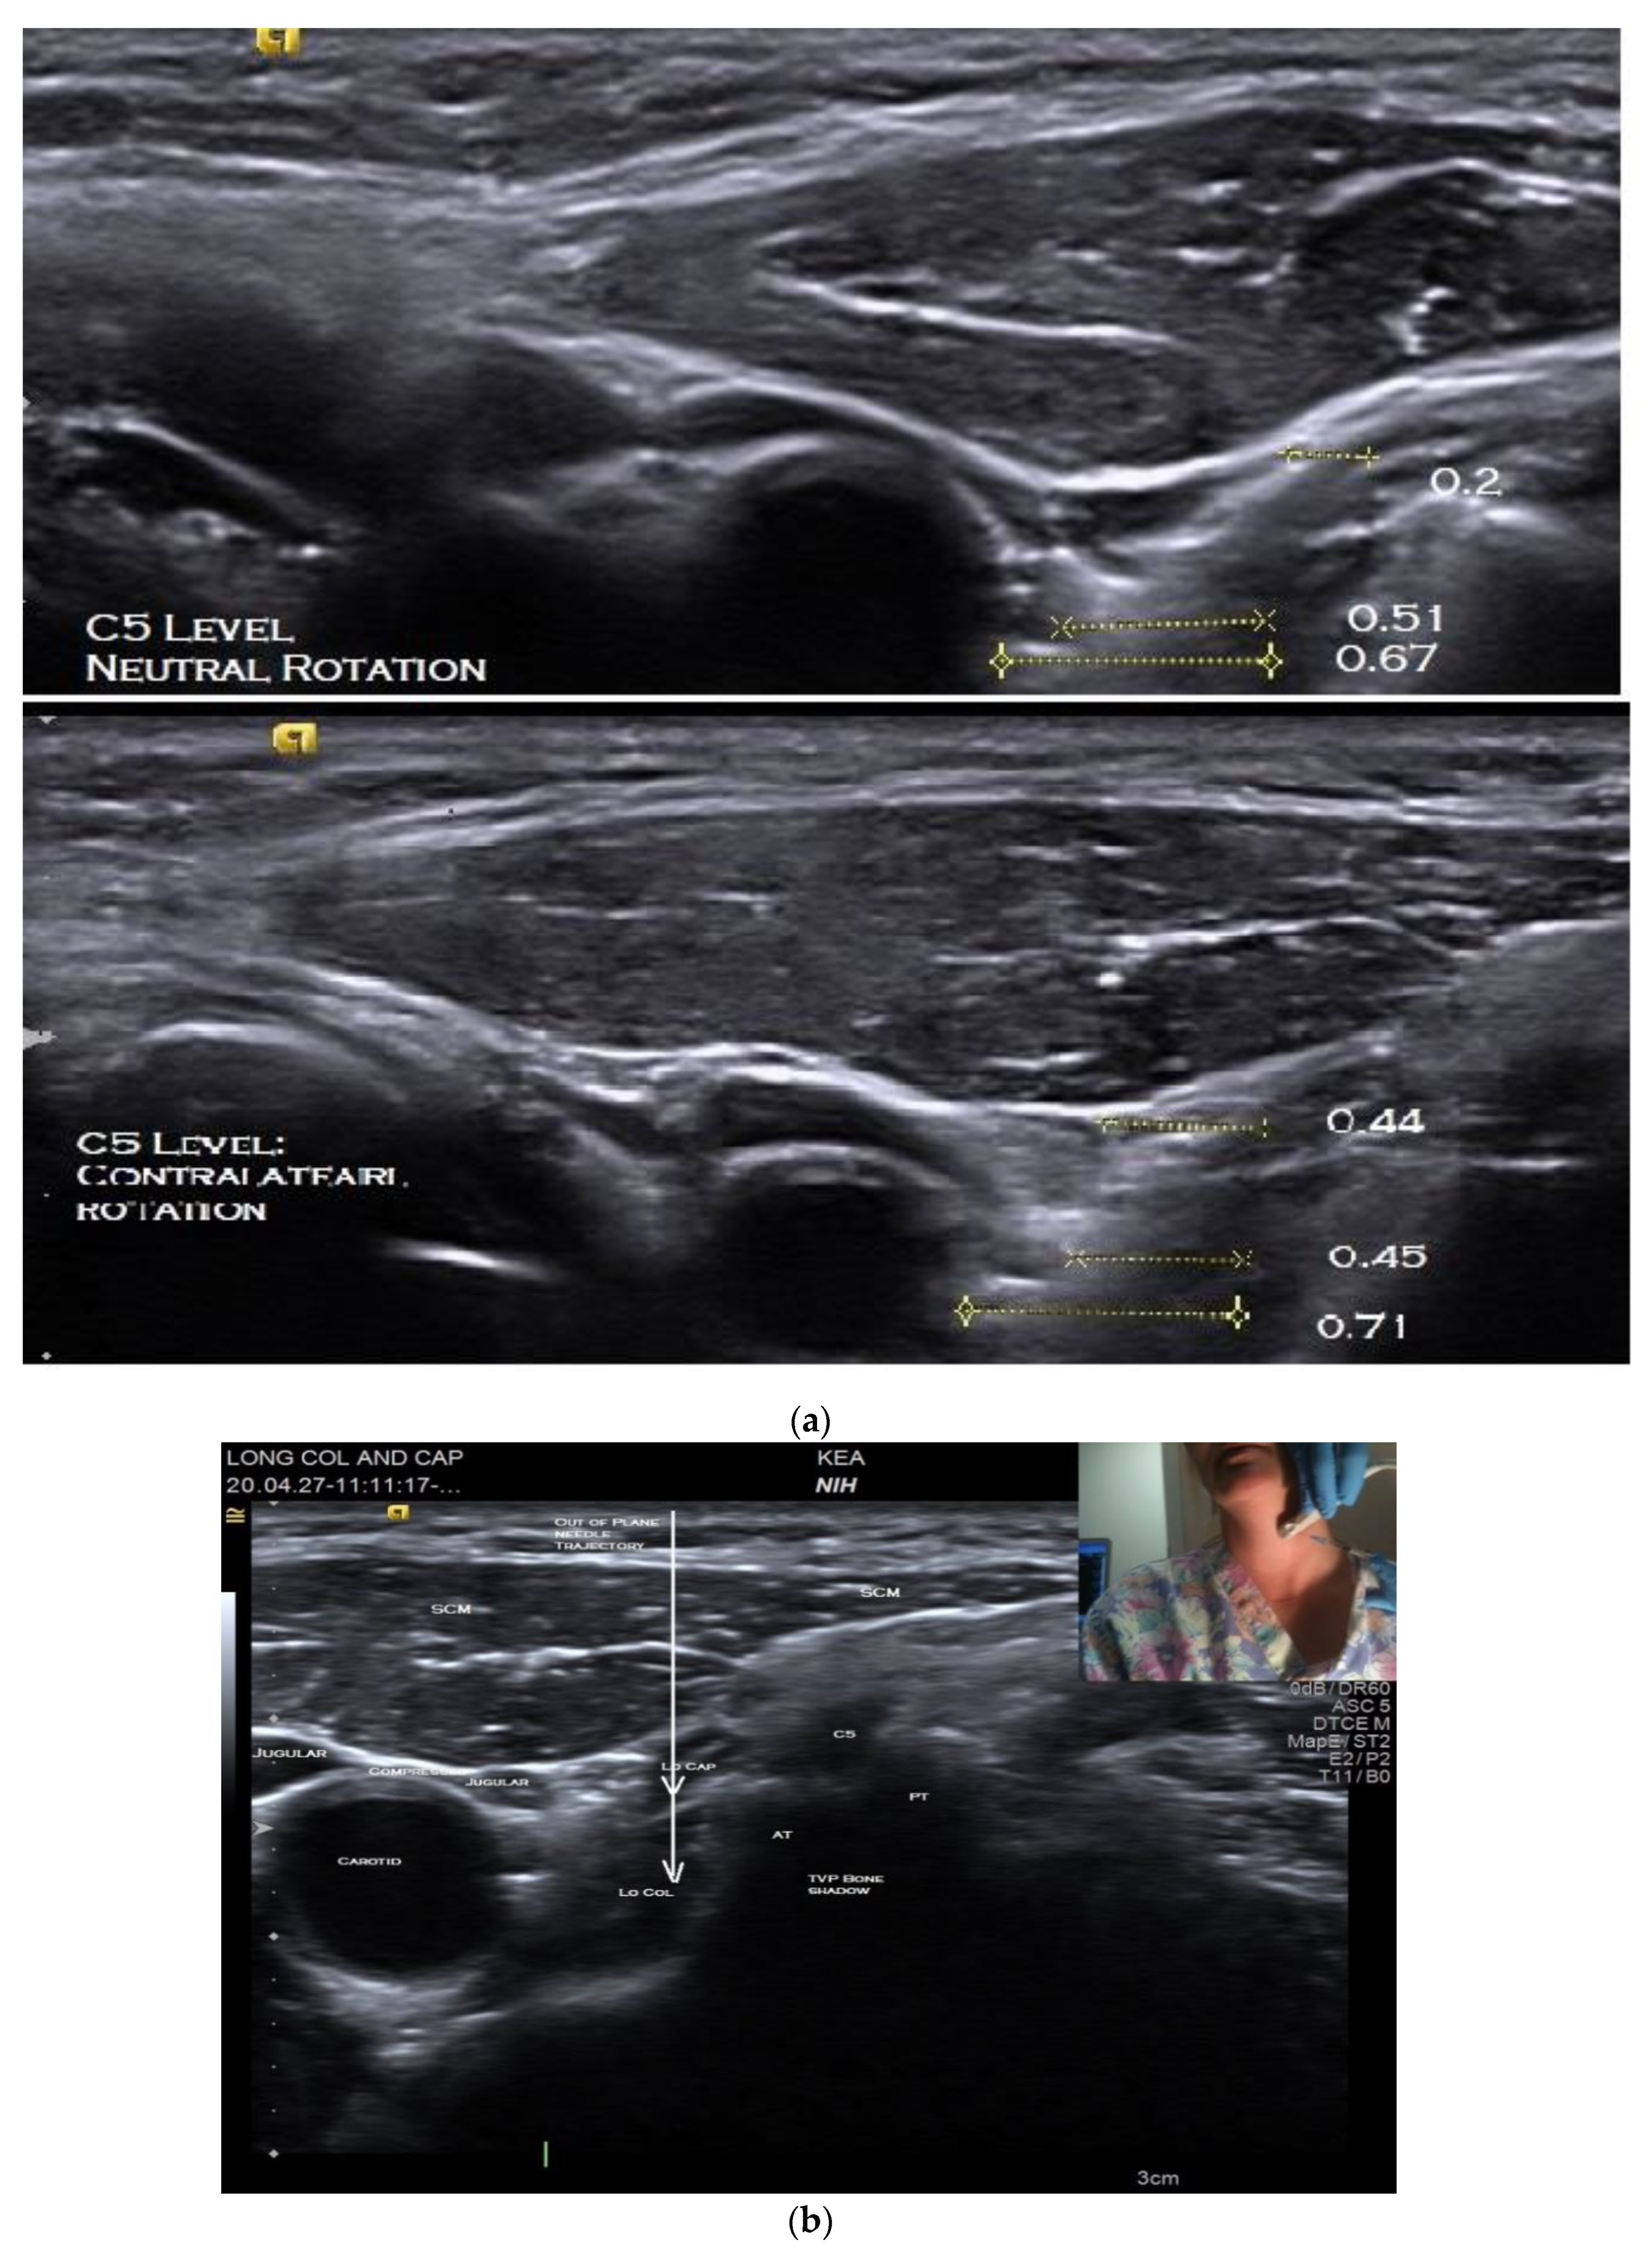

The patient is positioned seated on an adjustable examination chair, with the back of the chair sloped approximately 45 degrees backward and with the head resting on a headrest. Prior to injection, the US anatomy of the individual’s neck is thoroughly explored using both B-mode imaging in short and long axes and key structures identified. Scanning is performed with the neck in neutral rotation followed by maximal contralateral rotation, i.e., with the head turned away from the side to be injected. This is to determine if one position or the other provides the safest path to the target. Assessing the patient in both neutral and contralateral rotation is imperative as the optimal position may vary due to anatomic differences or rearrangements associated with dystonia (Figure 2a). An anatomic scan is also required to determine the depth of the target muscle/s so as to select the appropriate length of the injecting monopolar needle electrode.

Using this view, the LoCol and LoCap can then be identified lying anterior to the anterior tubercles of the cervical vertebra (Figure 2b). The LoCap lies anterior and slightly lateral to the LoCol muscle at this level. The two muscles are separated by a hyperechoic fascia which is easily identified (Figure 2b). With this view, it can be seen that the carotid and jugular vessels are more anterior and safely away from the planned trajectory of the needle to the muscles (Figure 2a,b). It can also be noted that the vertebral artery is posterior to the anterior tubercle, which helps to protect it from accidental puncture. Color Doppler imaging can be utilized to confirm location of critical blood vessels to avoid. The cervical nerve roots and trunks of the brachial plexus are also more posterior and can thus be circumvented. The transducer position should be adjusted to place the target muscles in the center of display screen.

The unique aspects of our approach compared to previously described approaches include (1) utilizing the anterior tubercles of the C5 and C6 cervical vertebrae as landmarks whereby the LoCap and LoCol are easily identified and, (2) evaluating the position of the patient’s neck in neutral and maximal contralateral rotation to determine which position creates the best path to the target by placing the carotid artery and sheath anteriorly relative to the muscles and the anterior tubercle. A prior study reported that maximum contralateral rotation of the neck for stellate ganglion blocks created the greatest distance between the carotid artery and the path of the needle to the target [18]. When utilizing this technique for BoNT injections in the LoCol/LoCap scanning in both neutral and contralateral neck rotation will determine which neck position provides the best access to the target muscles and greatest distance from the carotid artery.

In contrast, our proposed lateral approach avoids traversing the thyroid gland and also maximizes the anatomical distance between the needle and the carotid sheath, minimizing the risk of accidental puncture of this important vascular structure. A study by Park et al. investigated a similar technique for increasing the safety of US-guided stellate ganglion blocks; they found that the distance between the C6 anterior tubercle and the carotid artery was maximized with complete contralateral rotation of the head [18].

We typically perform these injections at the C6 level where there is overlap between the LoCap and LoCol so that both muscles can be targeted with a single puncture. This same approach can be used at the C5 level if it provides a clearer path to the muscles in the individual patient. At either level, the needle trajectory provides access to both muscles, with the needle first entering the LoCap from which it can be advanced into the LoCol. Injection below C6 is less desirable as below that level the LoCap is thinner and the LoCol lies deeper as it moves obliquely to insert on transverse processes in the upper thoracic region.

Figure 2. Short axis B-mode ultrasound images of longus capitis and colli muscles. (a) C5 level, in neutral position (top) and maximum contralateral rotation (bottom); (b) C5 level, with position of needle insertion and trajectory for out-of-plane injection and transducer position (inset).